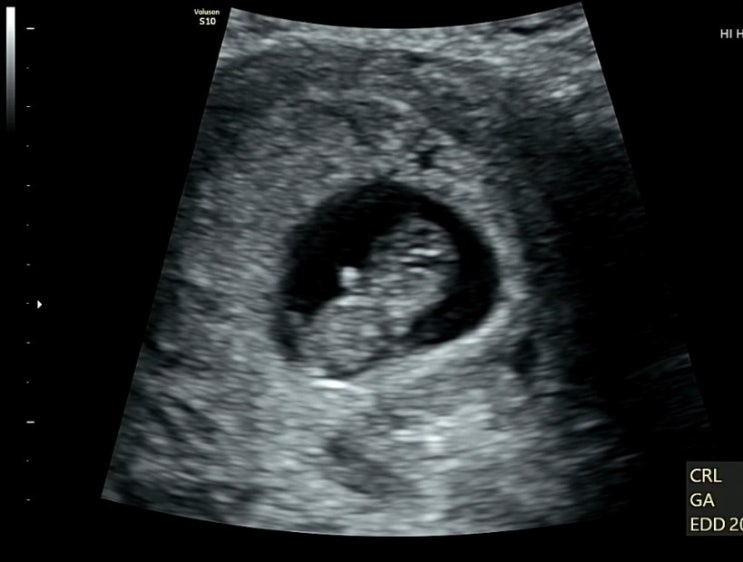

임신기록 ? ( 13주 ~ 16주 )

24/3/10 14w1d 13주차 부터 배가 슬슬 나오기 시작 신기하면서도 적응이 안됨 ㅠㅠ 주수에 비해서 배가 엄...